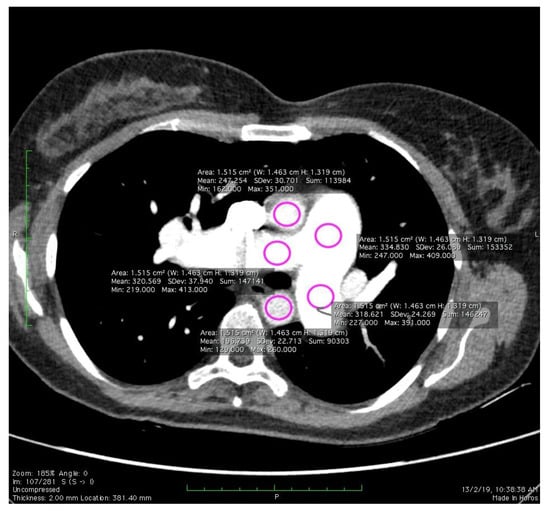

2.4. Image Quality Evaluation

- Christianson, O.; Winslow, J.; Frush, D.P.; Samei, E. Automated technique to measure noise in clinical CT examinations. Am. J. Roentgenol. 2015, 205, W93–W99. [Google Scholar] [CrossRef]